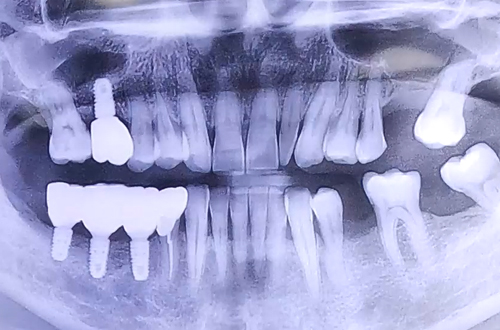

양쪽 모두 어금니 상태가 좋지 못하여 음식을 제대로 드시지 못하는 상태의 환자분 진료 내용입니다.

저희 더365치과는 임플란트에 특화된 진료를 진행하고 있어, 임플란트 후 '씹는 즐거움'을 되찾고 기뻐하는 분들을 볼 때 자부심을 느낍니다. ^^

진료일지를 통해서 그 일례를 살펴봐 주시기 바랍니다.